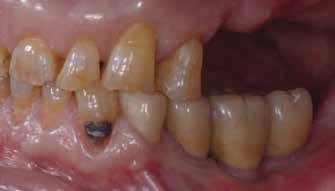

1. ábra: Műtét előtti fogászati panorámafelvétel, amelyen a hiányzó felső állcsont jobb első premolárisát és a szabad véggel rendelkező hidat láthatjuk. — 2. ábra: Az implantátum méreteinek megtervezése CBCT-vel. 3. ábra: Bukkális lágyrészdefektus. — 4. ábra: A biológiai szélesség értékelése a vertikális lágyszövetvastagság alapján. 5. ábra: Palatinális „tekercslebeny” – Palatal roll flap. — 6. ábra: Bredent medical copaSKY 4x10 implantátumbeültetés. 7. ábra: Szubkresztális implantátumbeültetés a várható biológiai szélességnek megfelelően.

8. ábra: Egyéni ínyformázó titánbázison, tulipán alakú emergenciaprofillal. — 9. a. ábra: A sebzárás okkluzális nézete.

(2. ábra). A lágyszövetek értékelése Seibert szerinti I. osztályú csontdefektust állapított meg (3. ábra), ezért a beavatkozáskor palatinális „tekercslebenyt” preparáltunk (palatal roll flap), és implantációt végeztünk, hogy kompenzálni tudjuk a bukkális lágyszövet-behúzódást. Megmértük a vertikális lágyszövetvastagságot, és úgy terveztük, hogy a szubkresztális implantátum beültetése összhangban legyen a biológiai szélesség kialakulásával a transzgingivális gyógyulási periódus alatt (4. ábra)

Az eljárást helyi érzéstelenítés mellett végeztük (4%-os articaine-hidroklorid 1:100 000 adrenalinnal). Papillakímélő, U alakú palatális bemetszést végeztünk, teljes vastagságú nyálkahártyalebeny preparálás történt, a lebenyt bukkálisan feltekertük (5. ábra). A lebeny bukkálisan feltekert részén de-epitelizációt végeztük el, amellyel kompenzálni tudtuk a bukkális lágyszöveti defektust. Szakaszos előfúrást végeztünk, és a bredent copaSKY 4x10 implantátumot 30 Ncm behajtási nyomatékkal helyeztük be (6. ábra). Az implantátumot 1 mm-re szubkresztálisan helyeztük be, hogy később szélesebb emergenciaprofilt tudjunk kialakítani (7. ábra). Az egyedi ínyformázó úgy készült, hogy kompozitot vittünk fel a titánbázisra, és így formáztuk a lágyszöveteket a transzgingivális gyógyulási fázis során (8. ábra). Az egyéni ínyformázó tulipán formájú, hogy kialakítsa a kívánt emergenciaprofilt. A lágyszövetet feszülésmentesen zártuk #6/0 nem felszívódó, monofil fonallal (Optilene, B. Braun Deutschland; 9. a–b. ábra). Posztoperatív röntgenfelvétel készült, ami alapján az implantátum a szomszédos fogakkal párhuzamos elhelyezést mutatott (10. ábra). Posztoperatív utasításokat adtunk a páciensnek a műtéti terület körüli szájhigiénia fenntartása érdekében. A beavatkozást követő egy héttel a varratokat eltávolítottuk, és a kezelt terület kielégítő gyógyulást mutatott (11. ábra). A 4 hónap utáni késleltetett terhelést a páciens kívánsága szerint terveztük.